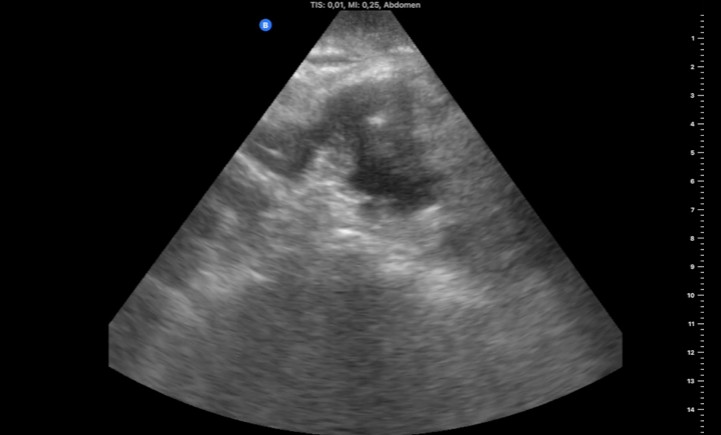

Hallazgos ecográficos

Masa ovalada de 5 x 2,6 x 4,7 cm, con pared gruesa hipoecogénica y zona central hiperecogénica (foto 1) que se prolonga por la parte craneal con el tubo digestivo (foto 2), sugestiva de neoplasia de colon.